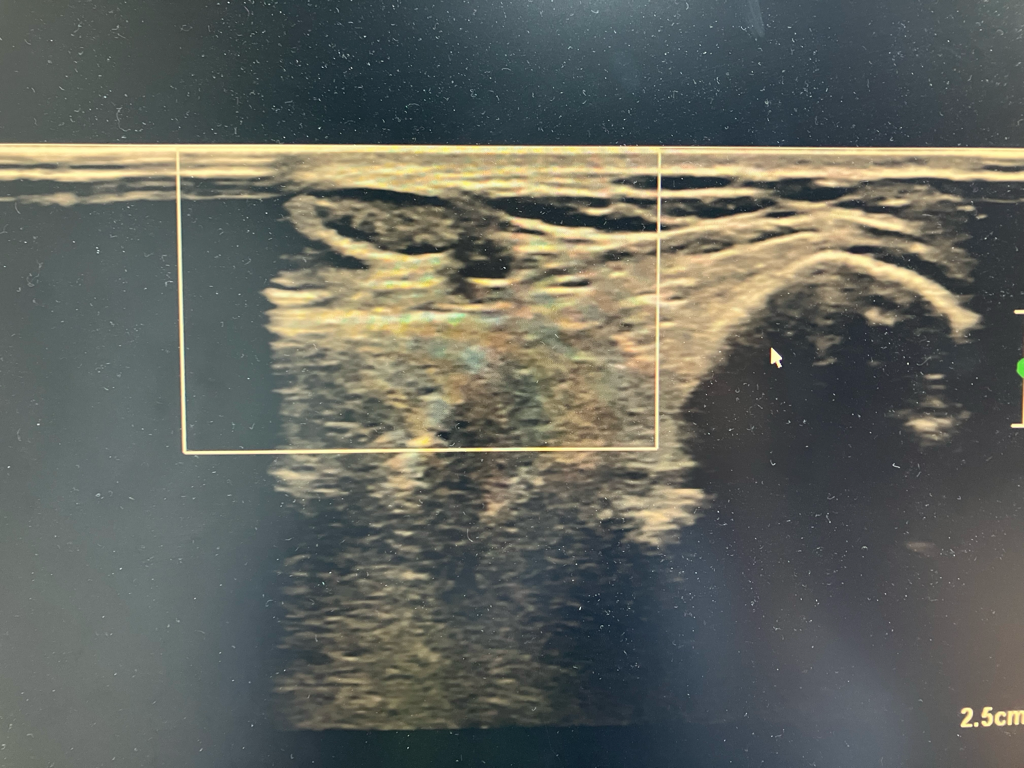

초음파는 이렇게 찍어놓은것만 보고 판단하기 어렵고 실시간으로 보면서 판단을 해야합니다.